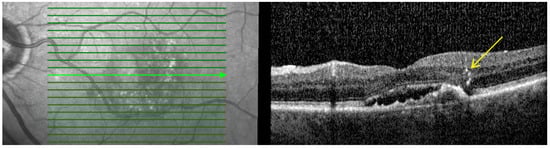

- Macular atrophy (MA): Characterized by in-lesion photoreceptor death and visual impairment and typically follows progressive atrophy and thinning of the retinal pigment epithelium (RPE) and choriocapillaris. The loss of photoreceptors can be detected by the thinning of the Henle fiber layer. This could be detected by OCT by features such as loss of the ellipsoid layer and outer limiting membrane as well as thinning of the outer nuclear layer, which together with the Henle fiber layer and photoreceptors appear as a single hyporeflective band on OCT images as shown in Figure 1 [24,25,26].